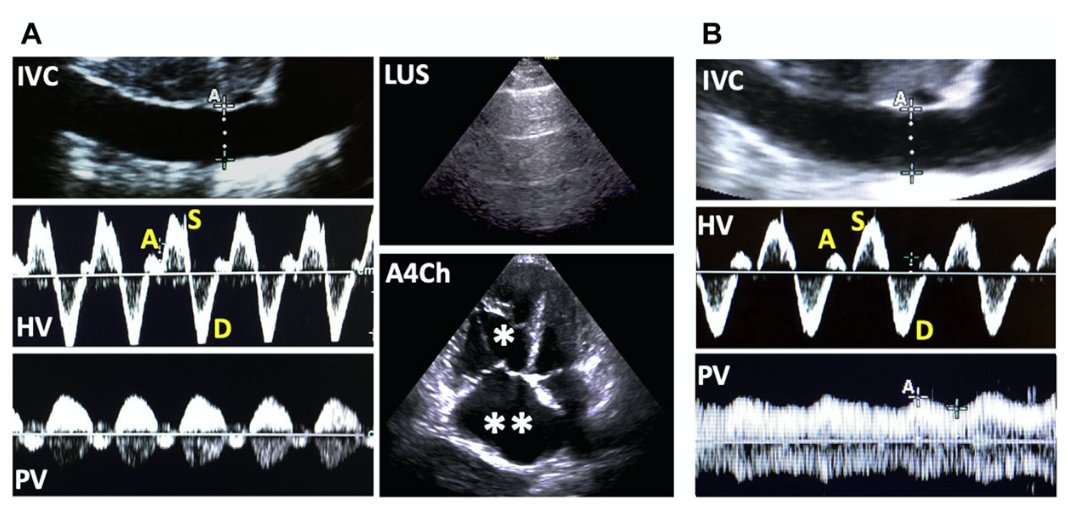

@NephroP

NephroPOCUS

3 years

A short 🧵 on hepatic vein #VExUS and key pathologies From: https://t.co/JcBQ8nqtvw 1/ HV Anatomy & Normal Flow Profile, respiratory variation (forward flow [S,D] ⬆️ during inspiration) Click ‘ALT’ for normal waveform description #POCUS #MedEd #Nephrology #IMPOCUS #FOAMed

4 years

Hepatic vein Doppler flash card. #VExUS #POCUS #MedEd #IMPOCUS

Simplistic representation of congestive nephropathy. #POCUS #VExUS #MedEd #Nephrology